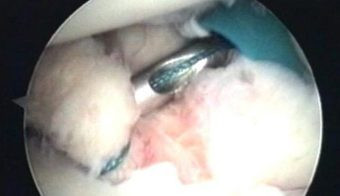

Con el uso de una fresa motorizada, se está preparando el lecho en el que se reinsertará la cápsula